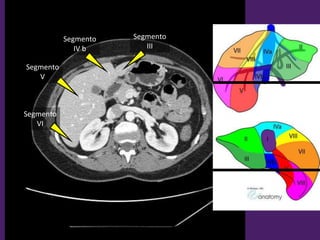

Segmento

III

IV b

VII

V

VI

L1-L2

L2